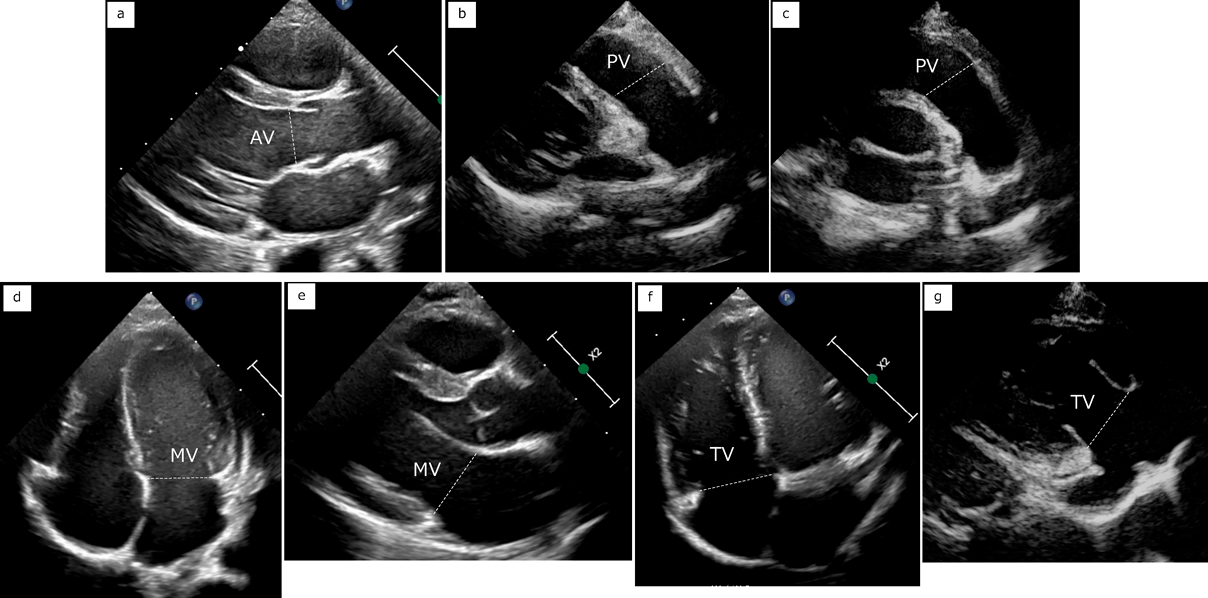

それぞれの弁輪と血管の計測を示す(Figs. 5, 6).いずれも最大となる時相で内膜面間の距離(trailing edge to leading edge)を計測する.僧帽弁輪径,三尖弁輪径は心尖部四腔断面と傍胸骨長軸断面でそれぞれ計測する.最大径となる拡張期で弁付着部を計測することが一般的であり,楕円形の房室弁輪形態を反映してそれぞれの計測部位で正常値が異なる.大動脈弁輪径は傍胸骨長軸断面で計測し,最大径となる収縮期で計測する.同様にバルサルバ洞径,接合部径,上行大動脈径も計測するが,これらの部位は成人ガイドラインにおいて拡張末期にleading edge to leading edgeでの計測が推奨されており,施設内での統一が望ましい.肺動脈弁輪径は収縮期の傍胸骨短軸断面で計測し,主肺動脈径,左右肺動脈径の計測も行う.症例によっては傍胸骨長軸断面のほうが描出しやすいことがある.大動脈弓は胸骨上窩断面から体位の工夫を併用して描出し,近位(無名動脈–左総頚動脈間),遠位(左総頚動脈–左鎖骨下動脈間),峡部(左鎖骨下動脈以遠の最狭部)を計測する.下大静脈は心窩部断面で下行大動脈との位置関係と流入する心房を確認し,右房に連続する断面で計測するとともに呼吸による変動を観察する.肺静脈は心尖部断面と胸骨上窩断面で左房への流入を確認する.冠動脈は傍胸骨短軸断面の大動脈弁レベルから左右冠動脈起始部を描出し,流速を下げたカラードプラを併用する.

Pediatric Cardiology and Cardiac Surgery 41(1): 20-27 (2025)

Fig. 5 Measurements of valves

a. Aortic valve with parasternal left ventricular long axis view. b. Pulmonary valve with parasternal right ventricular outflow tract view. c. Pulmonary valve with parasternal short axis view. d. Mitral valve with apical four chamber view. e. Mitral valve with parasternal left ventricular long axis view. f. Tricuspid valve with right ventricular focused apical four chamber view. g. Tricuspid valve with parasternal right ventricular inflow view. AV, aortic valve; MV, mitral valve; PV, pulmonary valve; TV, tricuspid valve.